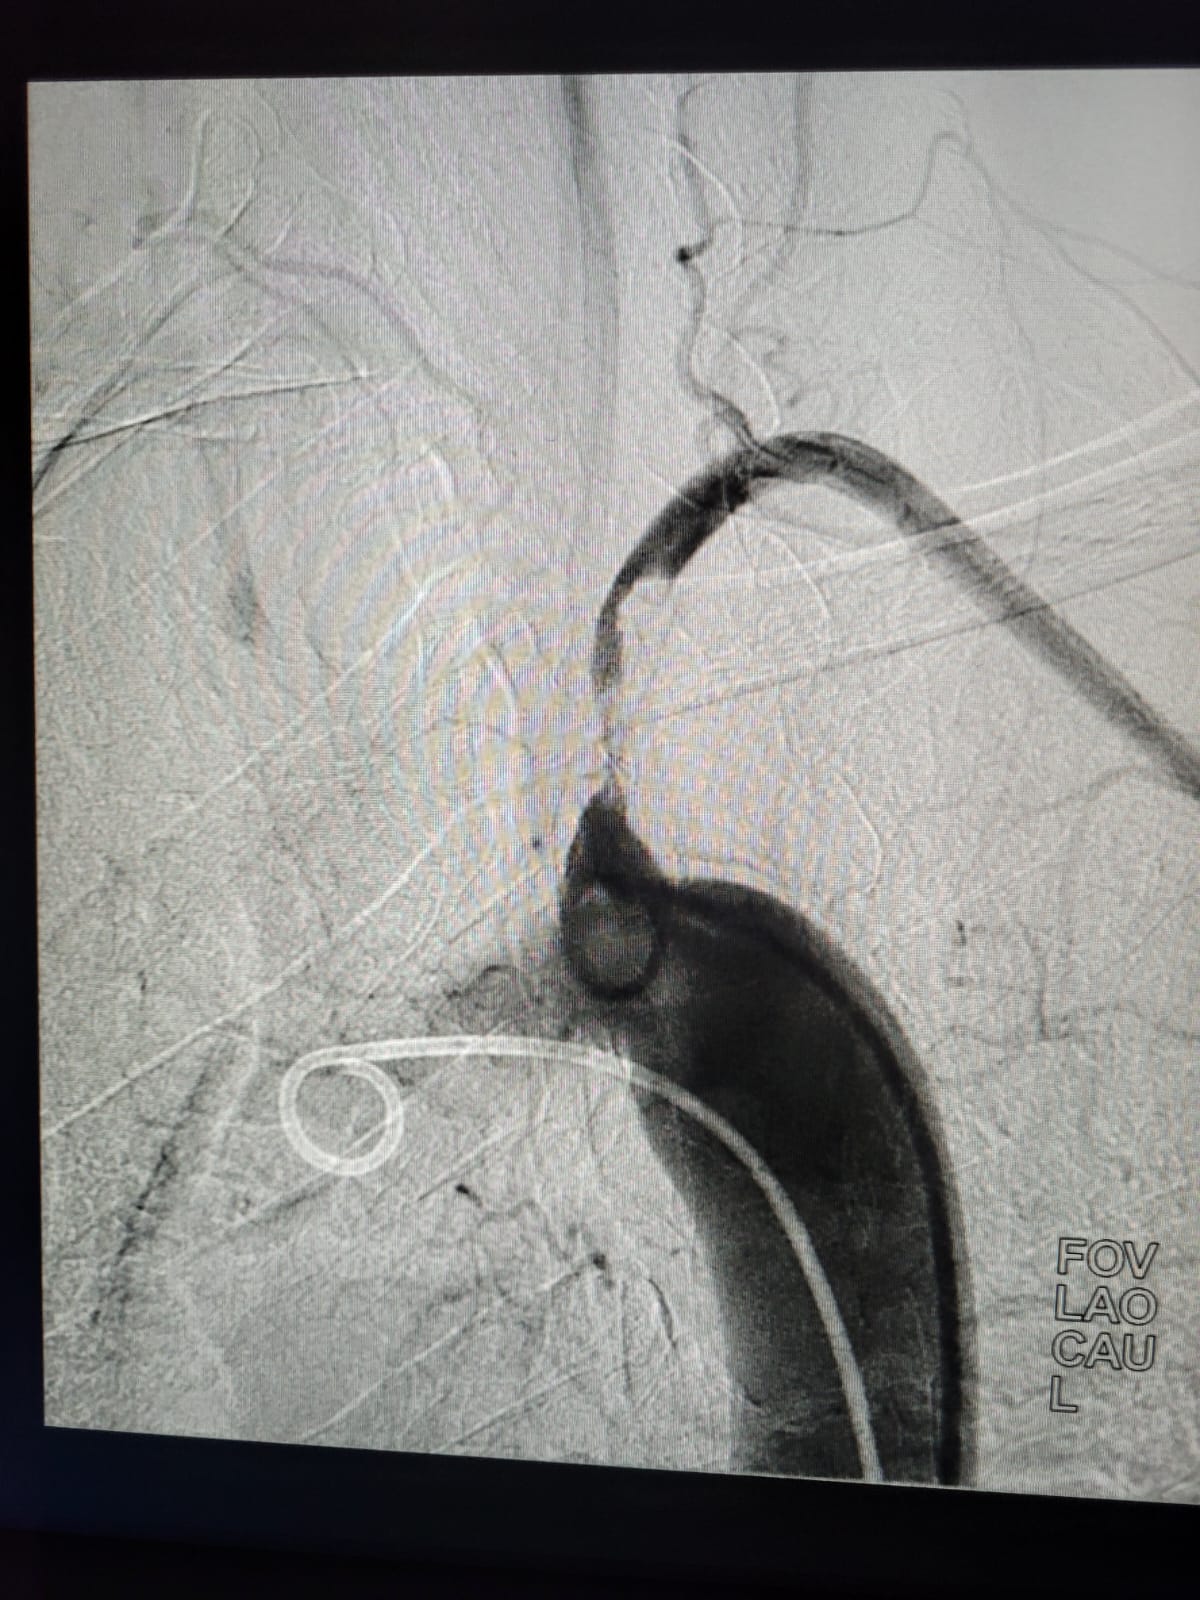

Emergency and Difficult Coronary Angiography / Angioplasty